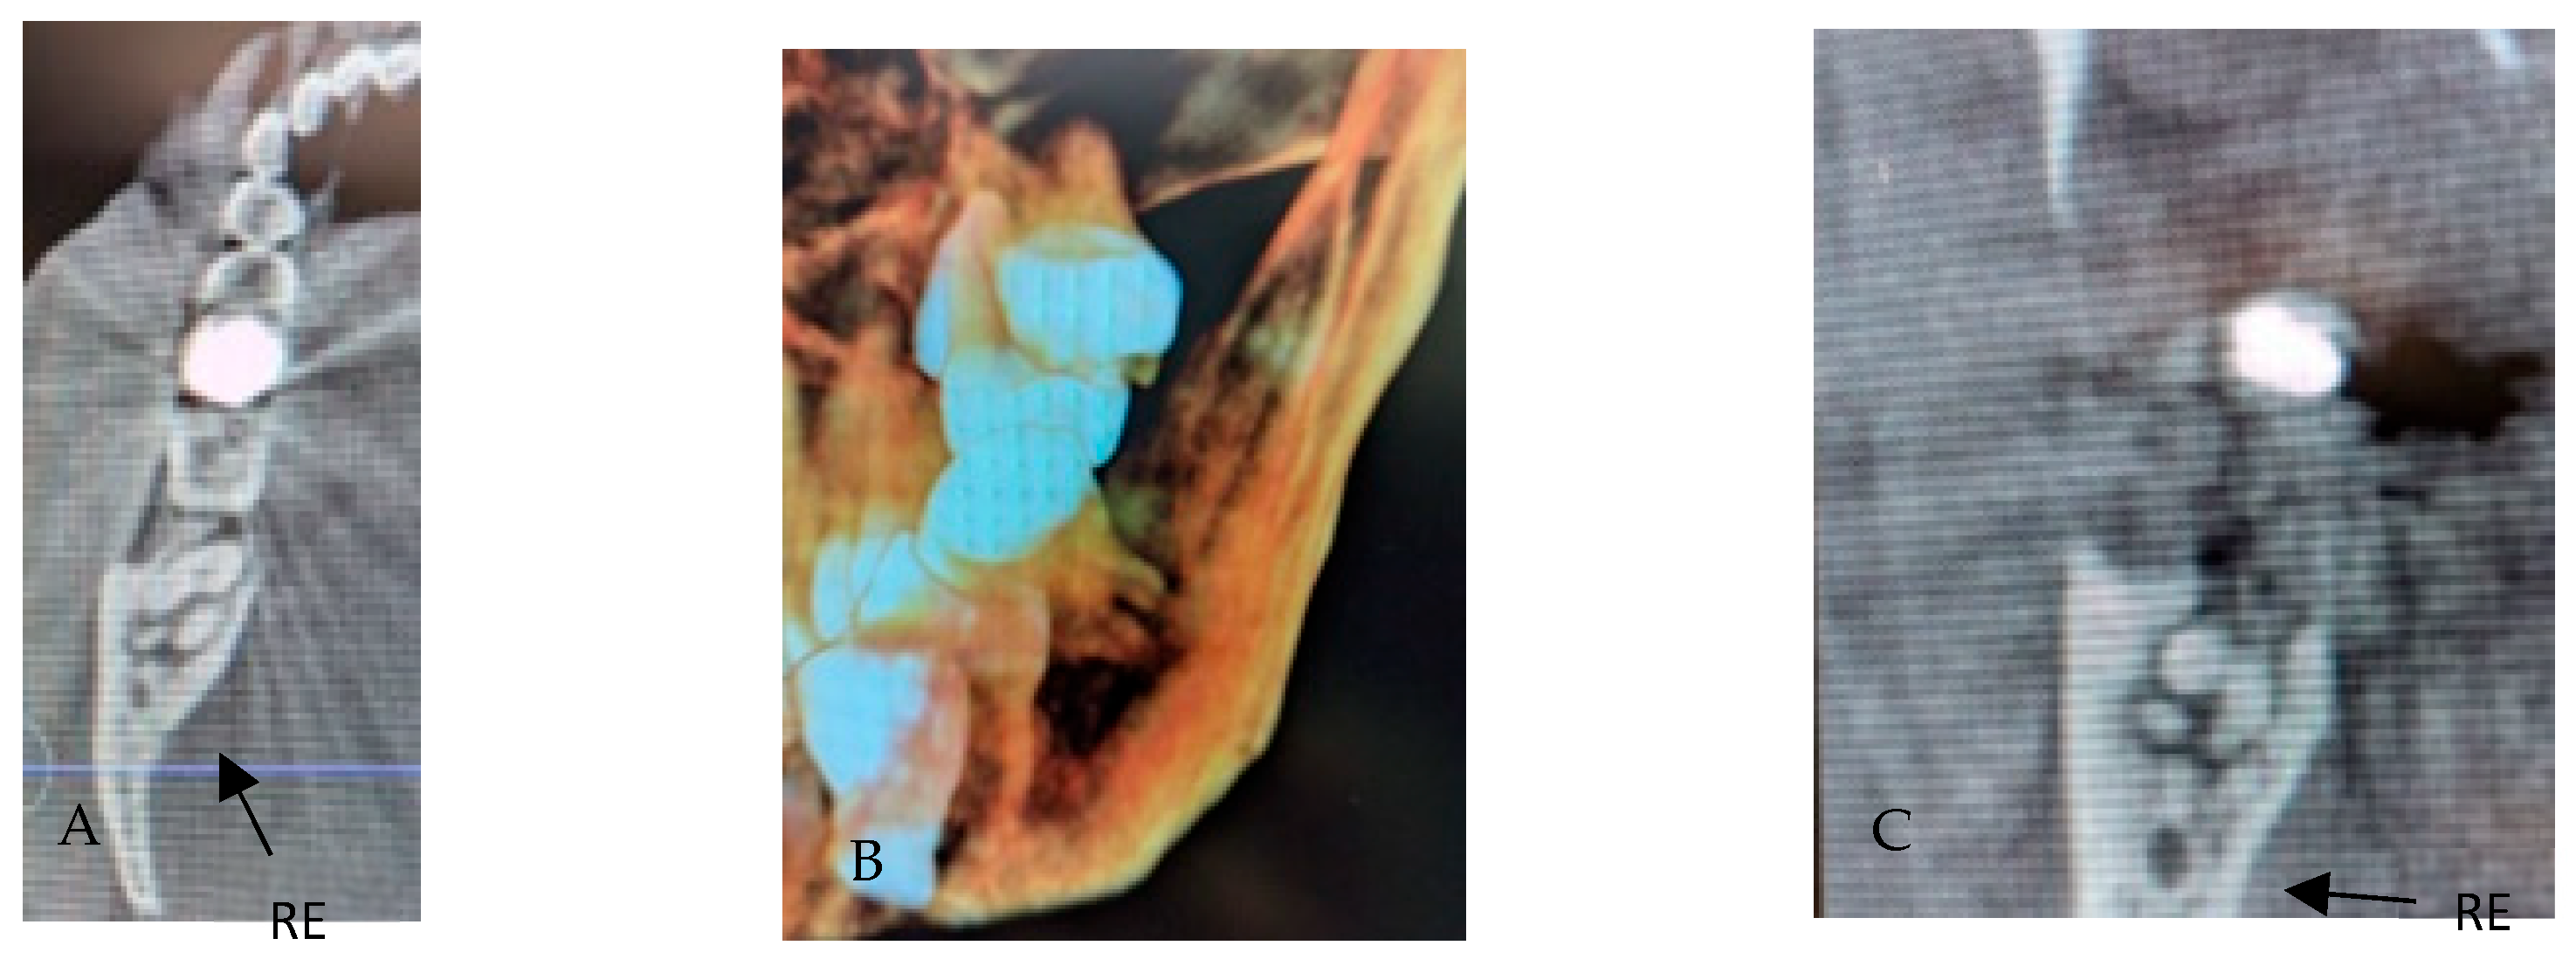

3.2. Radix Entomolaris

- Type I: straight root/canal;

- Type II: curvature in the coronal third, followed by a straight continuation;

- Type III: curvature in the coronal third with an additional buccal curvature in the apical third.

3.3. Radix Paramolaris